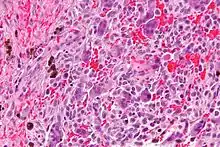

| Micrograph of a central giant cell granuloma showing the characteristic giant cells with surrounding cells that have nuclei that are dissimilar to those in the giant cells. H&E stain. | |

Histology of CGCG shows a lobulated mass composed of vascular connective tissue and multinucleated giant cells (osteoclasts). The giant cells may be diffusely located throughout the lesion or focally aggregate in the lesion, often clustered around hemorrhagic areas hemosiderin deposits. Lobules of the lesion can be separated by fibrous tissue or even thin layer of bone or osteoid that can be seen radiographically. Giant cells are thought to form in response to signals produced by fibroblasts and blood vessels or as a response to cytokines.[2][5]